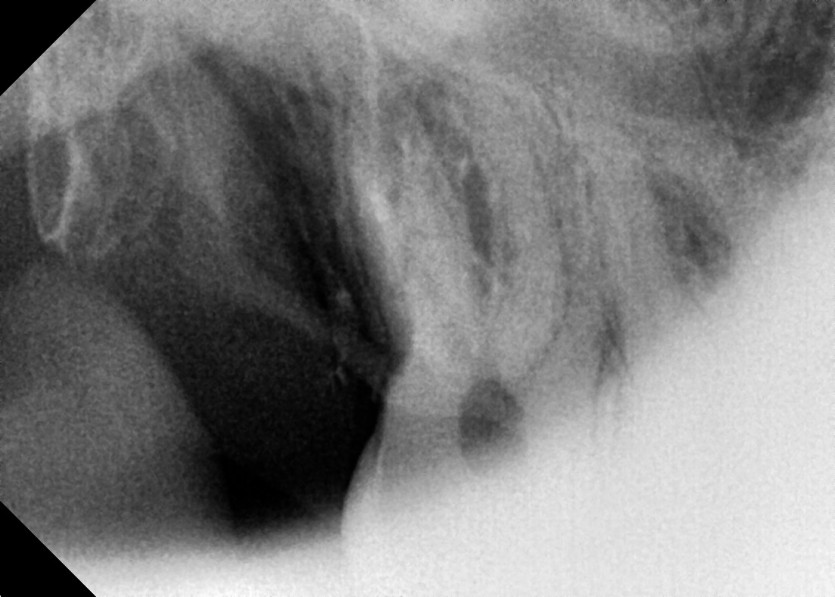

#18,28,38,48 사랑니 발치

구강 외과 전문의가 당일 발치했습니다.